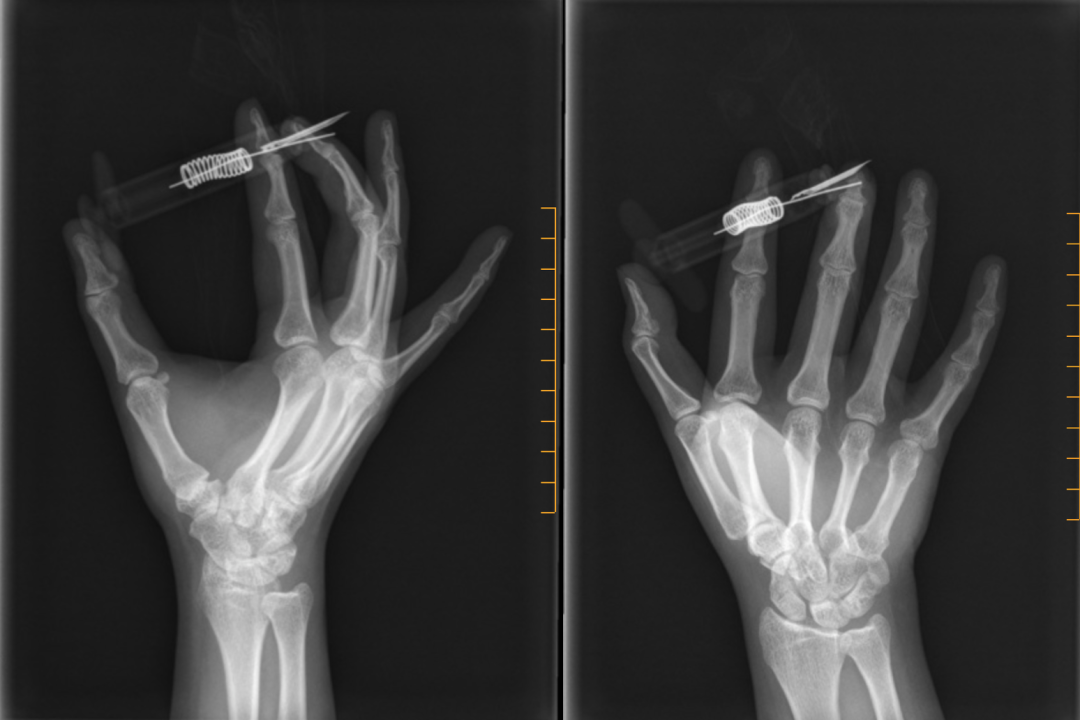

急诊拍x线片两张|作者供图

晋先生拍的片子显示骨折